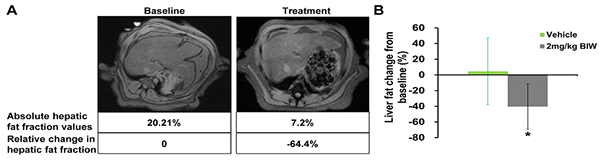

B1344對高脂飲食喂養的食蟹猴脂肪肝的治療作用

符合入選標準的肥胖食蟹猴接受B1344治療或對照處理,第69天通過磁共振成像(MRI)測定肝臟脂肪。(A)經每周兩次給予2 mg/kg B1344治療后的猴子肝臟脂肪含量的MRI測量結果;(B)經每周兩次給予2 mg/kg B1344治療后的猴子肝臟脂肪含量的定量測定結果。